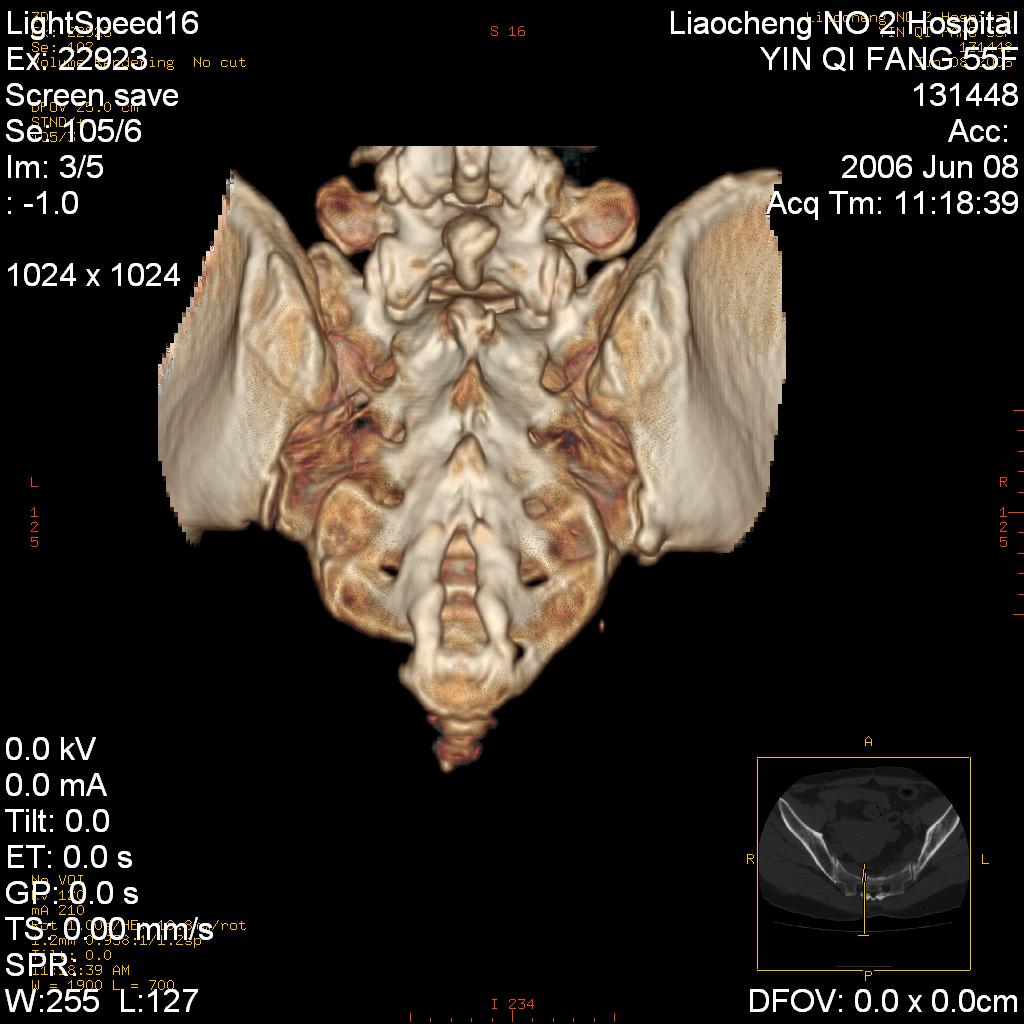

女,55岁,十余年前骶尾骨摔伤,x线平片诊断骶骨裂纹骨折,现在骶尾部又疼痛2月,x线怀疑骶骨左下部骨质破坏。大家看看,是不是先天变异。正常人不是只有4个骶孔吗?怎么此病例有5个?

两侧骶髂关节炎,确实做得很漂亮

众口一词啊,图象确实漂亮,羡煞人也!右侧骶髂关节间隙变窄,相对缘增生硬化,髂骨侧增生明显。左侧轻微类似改变,考虑双侧骶髂关节炎。余未见异常。

考虑双侧骶髂关节炎。余未见异常。

支持骶髂关节炎,3d做得很漂亮!!!!

五个孔也是正常的呀;